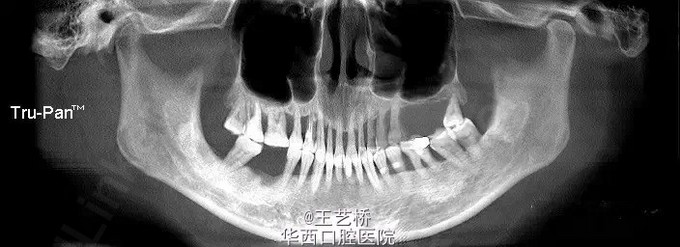

各式各样形态的上颌窦(二)

接着之前放图